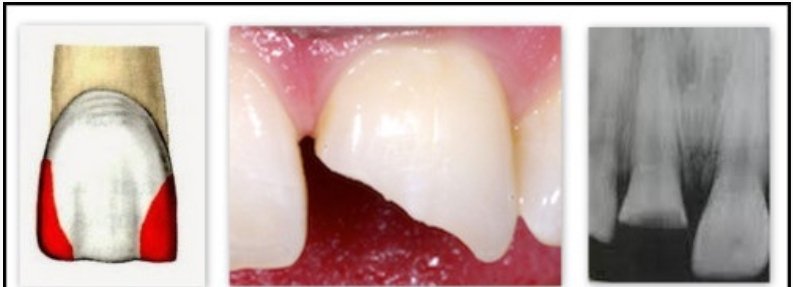

3 класс - это полости, расположенные на контактной поверхности резцов и клыков без нарушения режущего края.

4 класс - это полости, расположенные на контактной поверхности резцов и клыков с нарушением режущего края.

5 класс - это полости, расположенные в пришеечной области всех зубов.

2. Поверхностный кариес: на месте пятна образуется полость с нарушением целостности тканей. Возможны кратковременные реакции на сладкое, кислое, холодное. Кариес приближается к эмалево-дентинной границе.

3. Средний кариес - кариозный процесс полностью прошел всю толщу эмали и попал в поверхностные слои дентина. Скорость распространения патологического процесса в разы быстрее из-за анатомии дентина. Симптоматика не отличается от поверхностного.

4. Глубокий кариес - процесс затрагивает глубокие слои дентина и движется по направлению к пульповой камере. Значительная полость, кратковременные боли от физических и химических раздражителей, проходящие сразу после их удаления.